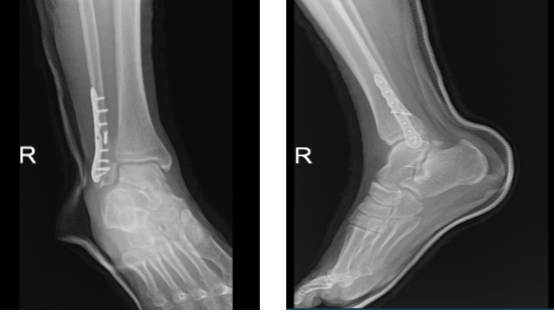

After three weeks from the surgery, the patient went to the office with X-ray results, for his follow up checkup. The skin of the patient peeling over the incision is resolved, the walking boot PWB 25%, to increase gradually with the help of the ice, elevation and OTC anti-inflammatory meds, the patient is doing very well after the surgery.

The surgical plate and screws transfix a fracture of the distal right fibula. Alignment is near anatomical, there is no significant interval change, the distal tibia is intact. There are no significant degenerative changes, the Ankle mortise is well maintained. There is no appreciable soft tissue swelling and no calcaneal plantar spur.

X-ray right ankle - 3 weeks after surgery

X-ray right ankle – 3 weeks after surgery